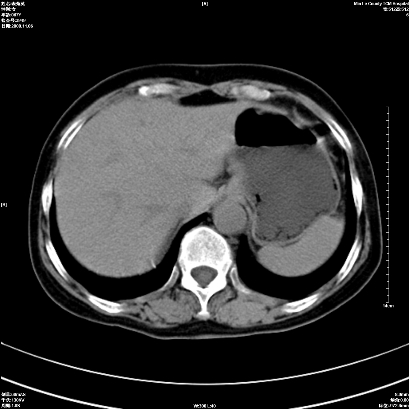

以下是引用卜一在2008-11-6 15:58:00的发言:[br]胰头略增大,胆总管扩张,末端渐行性狭窄。多考虑:胰头癌!建议增强!